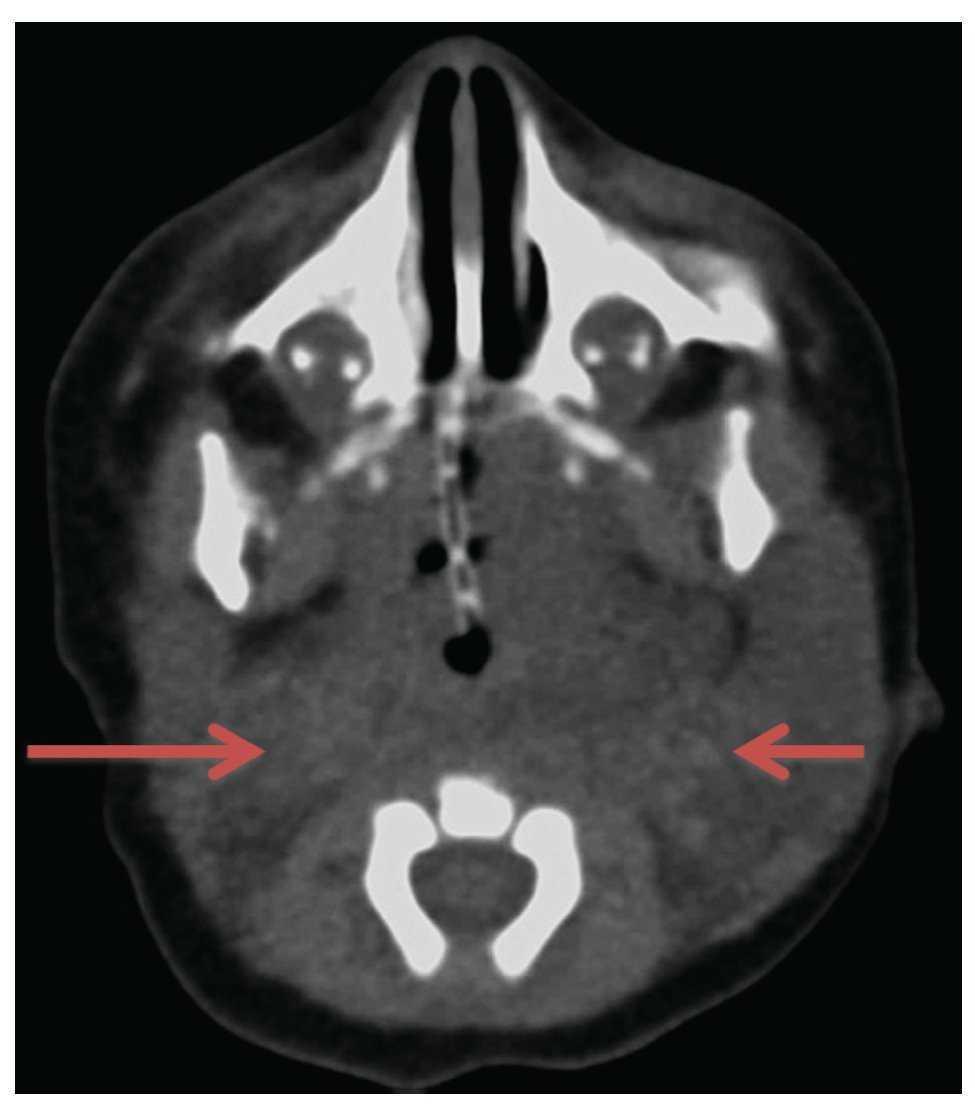

Due to clinical and radiological findings, a pediatric surgery consultation was requested. It was decided that the patient was not a candidate for resection due to the location, extent and involvement of adjacent organs. Because of the decision to not resect the mass, a less invasive option was sought. Based on the experience of the pediatric radiologist in the management of this type of cystic lesion, administration of pure ethanol (100%) was proposed in an infiltration of 0.5-1 ml in eight sessions, one every 2 weeks, using an ultrasound-guided procedure (Fig. 4). After eight sessions, using nuclear magnetic resonance, we documented the decreased volume of the CH and, as a result, increased oropharyngeal space and release of a major gastrointestinal and respiratory area, which allowed autonomous breathing and feeding by mouth.

Figure 4 Insertion of the needle through a lobe of the cyst (arrow).